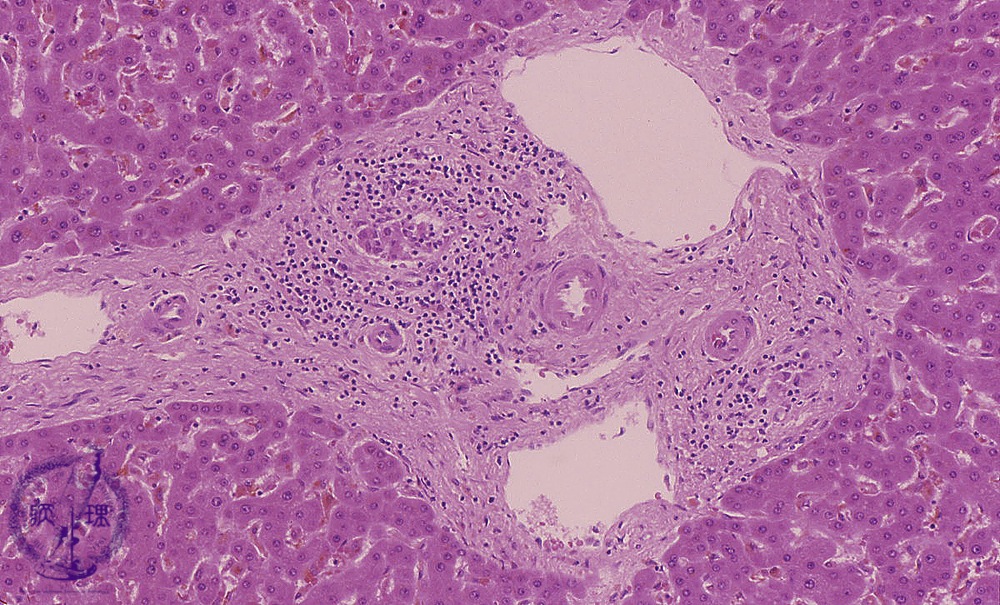

• (11)Transplantation rejection

Microscopic image (HE stain, intermediate power): Mid-sized portal areas show fibrosis and inflammatory infiltrates composed mainly of lymphocytes. Damaged (?) interlobular bile ducts, surrounded by an inflammatory reaction, are gradually destroyed.